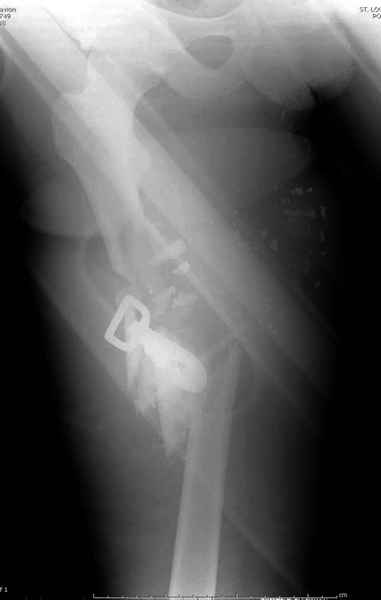

2 перелом бедра

3 такие раны после удаления пули и остатков одежды можно закрыть первично